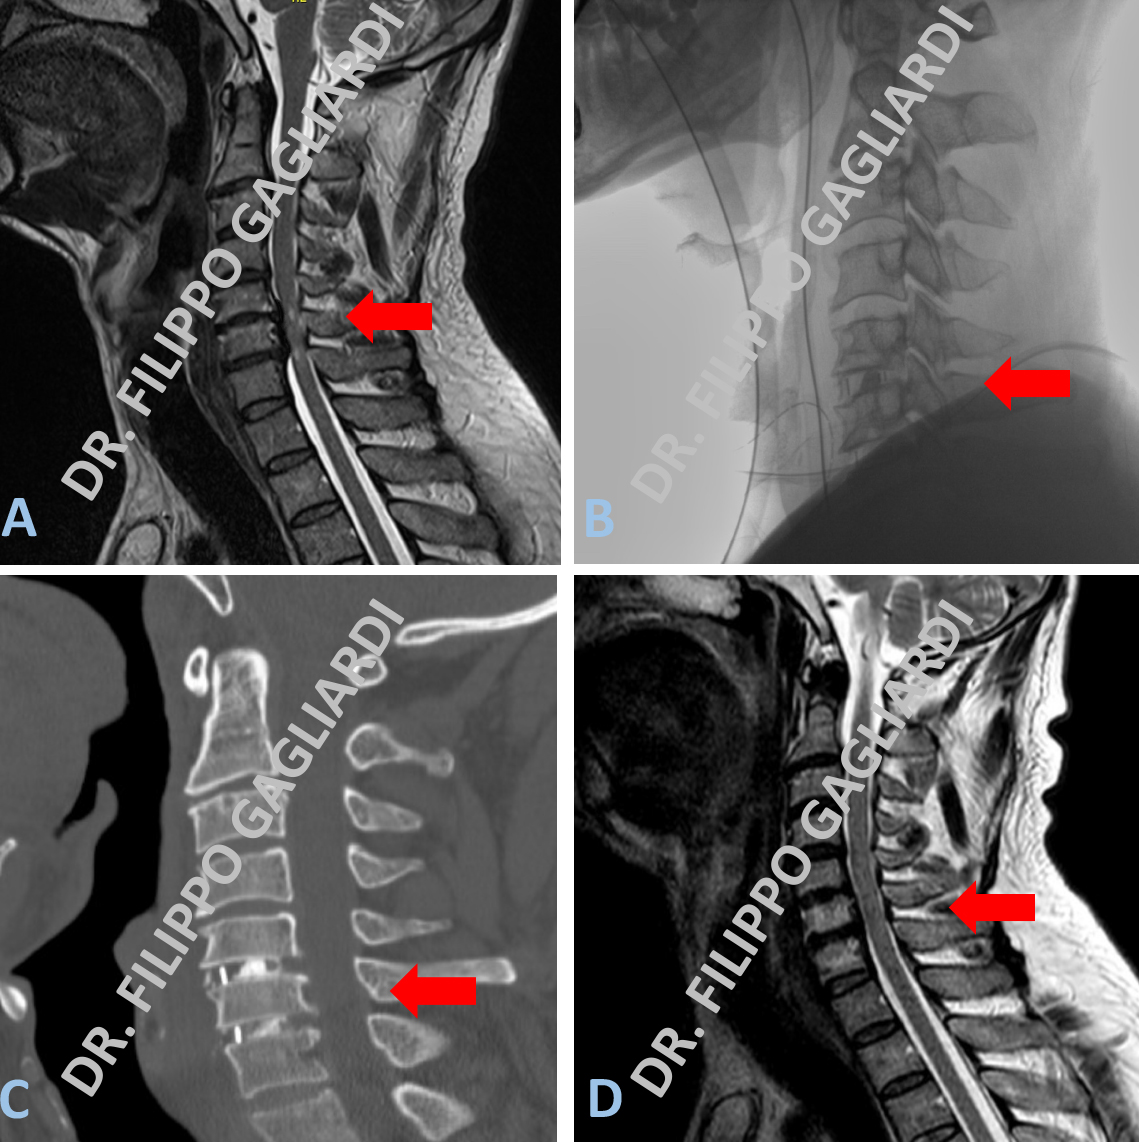

Ernia del disco cervicale Caso di doppia ernia del disco cervicale tra la quinta (C5) e sesta (C6) vertebra cervicale e tra la sesta (C6) e settima (C7) vertebra cervicale. Le ernie condizionano una grave compressione sul midollo spinale che appare schiacciato e sofferente. Il Paziente si presentava con un grave impaccio motorio agli arti inferiori e conseguenti problemi a camminare. La Figura A mostra la RM pre-operatoria dove si possono apprezzare le due ernie e la compressione del midollo spinale (freccia rossa). Il Paziente è stato sottoposto ad un intervento di doppia microdiscectomia cervicale per via anteriore. La Figura B mostra la lastra eseguita in sala operatoria per il controllo della procedura. I dischi malati sono stati rimossi ed al loro posto sono state posizionate due gabbiette in titanio (freccia rossa). Questo mantiene i rapporti anatomici tra le vertebre e dá stabilità alla colonna vertebrale. Lo si può apprezzare alla TC della colonna cervicale eseguita dopo l’intervento (Figura C) La RM cervicale eseguita a 6 mesi dall’intervento dimostra la asportazione completa delle ernie (freccia rossa) e la decompressione del midollo spinale (Figura D).